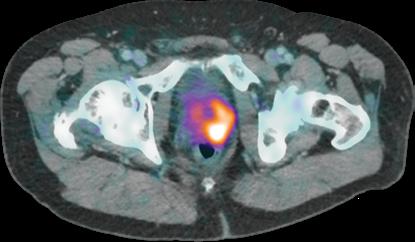

In the 2020-21 issue of Images, we shared the story of the U.S. Food and Drug Administration’s approval of Prostate-Specific Membrane Antigen (PSMA) PET imaging, based on research conducted at UC San Francisco and UCLA. The technique uses positron emission tomography in conjunction with a PET-sensitive drug that is highly effective in detecting prostate cancer throughout the body so that it can be better and more selectively treated. The PSMA PET scan also identifies cancer that is often missed by current standard-of-care imaging techniques.

In September 2021, a team led by Thomas Hope, MD, at UCSF and Jeremie Calais, MD, at UCLA, published a paper in JAMA Oncology (doi:10.1001/ jamaoncol.2021.3771) detailing the phase 3 diagnostic efficacy trial that led to FDA approval of PSMA PET.

What is the main focus of the JAMA Oncology paper?

The paper focuses on the role of 68Ga-PSMA-11 PET at time of initial staging. The goal was to compare the imaging results to nodes found at time of surgery in order to determine the sensitivity and specificity of PSMA PET. This study showed that PSMA PET has a high specificity for the detection of nodal metastases, although the sensitivity for small pelvic nodes was lower than expected.

Next up is to grow the use of PSMA PET for patient selection in PSMA radioligand therapy.

Currently there are no FDA approved agents for PSMA radioligand therapy, but we expect approval of 177Lu-PSMA-617 in the coming months, and so we will start using PSMA PET in this patient population.  Additionally, now that PSMA PET will be widely available, we will need to complete clinical trials in order to understand how to manage patients better based on the results of PSMA PET imaging studies. 

PSMA PET scan identifies cancer that is often missed by current standardof-care imaging techniques.